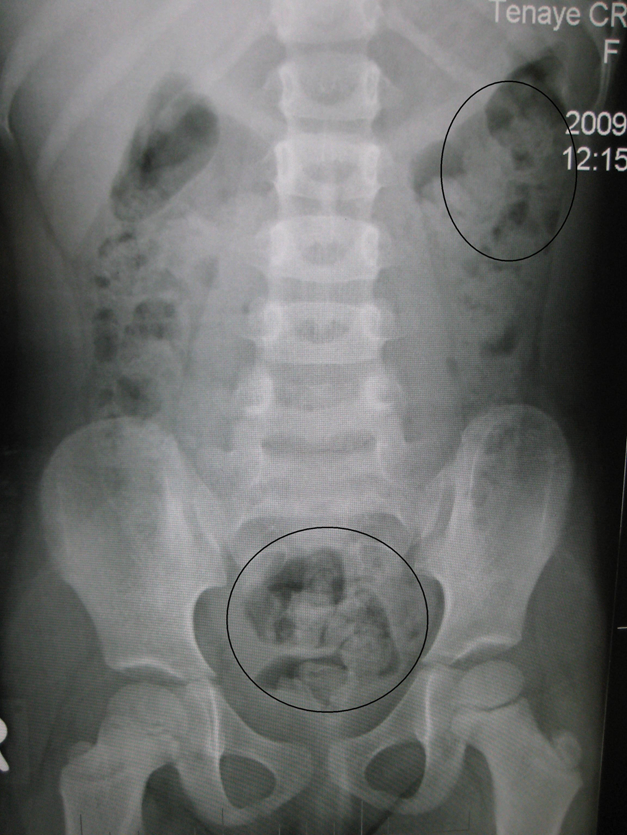

2) AXR

(1) 원리: Radiopaque한 표지자를 복용한 뒤 일정 시간(≒ 5일) 후 AXR을 촬영해 얼마나 대장에 남아있는지 측정

* 표지자와 AXR 대신 방사선동위원소와 핵의학적 스캔을 대신 이용하기도 한다.